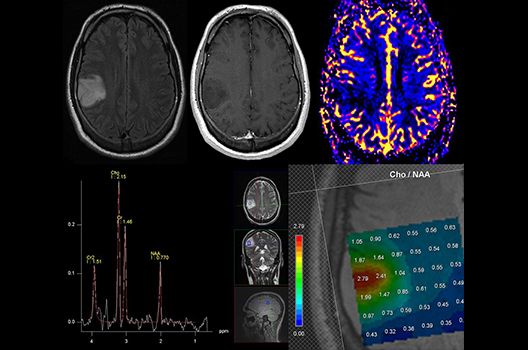

Die Magnetresonanztomographie (MRT) ist ein Verfahren, bei dem durch magnetische Kräfte Bilder des Körperinneren angefertigt werden. In der Neuroradiologie können manchmal kleinste Veränderungen schwere Folgen haben; daher forschen wir an der Entwicklung hochauflösender MRT-Sequenzen, mit denen diese Prozesse und auch einzelne Nervenfaserbahnen sichtbar gemacht werden können. Darüber hinaus sind bei vielen Erkrankungen des Gehirns die Blutgefäße betroffen. Daher arbeiten wir an der Neu- und Weiterentwicklung von MRT-Sequenzen zur Darstellung der Blutgefäße und zur Blutflussanalyse (sog. „Angio-MRT“). Einen besonderen Forschungsschwerpunkt unserer Klinik stellen die MR-Protonenspektroskopie und die funktionelle MRT dar, mit denen die Analyse einzelner chemischer Substanzen im Hirngewebe oder die Darstellung ausgewählter Hirnfunktionen möglich ist.

Die Hybridbildgebung mittels PET/MRT spielt insbesondere in der onkologischen Bildgebung eine wichtige Rolle. Eine mögliche Fragestellung ist die Unterscheidung zwischen einem Tumorrezidiv oder therapeutisch assoziierten Veränderungen insbesondere dann, wenn diese Frage mittels MRT alleine nicht beantwortet werden kann.

Die bildgebende Diagnostik und Verlaufsbeurteilung von Tumoren des Nervensystems ist einer der klinischen und Forschungsschwerpunkte unserer Abteilung. Eine besondere Bedeutung kommt der Hybrid-Bildgebung zu. Das Universitätsklinikum verfügt über einen integrierten Ganzkörper-PET/MRT-Scanner, der die Vorteile der MRT-Bildgebung und der Positronenemissionstherapie (PET) vereinigt. Aufgrund der langjährigen klinischen Arbeit und Forschungstätigkeit mit diesem Gerät hat die Neuroradiologie Tübingen maßgeblich zur Etablierung dieses Verfahrens beigetragen. Auch weiterhin forschen wir intensiv an neuen Methoden zur frühen Einordnung von Tumoren und insbesondere Tumorrezidiven, die mit anderen Methoden häufig nicht erfasst werden können.